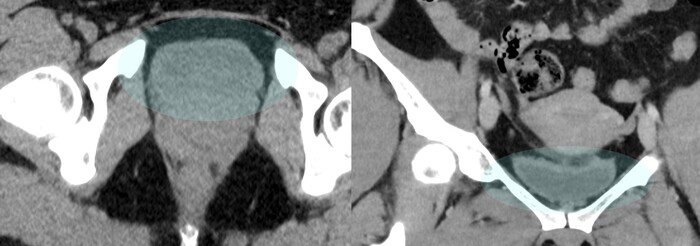

Почки без видимой патологии, особенно правая почка без камней или признаков застойности (чашечно-лоxаночная система не расширена). Особенно правый мочеточник практически не прослеживается, что очень хорошо: значит он не расширен, просвет пуст:

Мочевой пузырь пуст (за исключением небольшого количества мочи), а значит выход камня в его просвет тоже можно исключить:

Однако в малом тазy, в области правого яичника было обнаружено округлое образование с чёткими контурами и размером 4 х 4 см, которое содержало преимущественно жир и некоторые плотные включения:

Дополнительно обращал на себя внимание геморрагический (с примесями крови) выпот в дугласовом пространстве:

Со средней плотностью 29 HU (вода 0 HU- +10 HU, жир -200 HU - 0 HU, вода с примесями крови - выше +20 HU):

С определением типа образования правого яичника проблем особых не было: так выглядит классическая зрелая тератома на КТ.

Проблема была больше в выпоте с кровью в малом тазу, т.к. это не нормально (у женщин детородного возраста допускается некоторое количество свободной жидкости в малом тазу, но в совсем небольших и без значительных примесей крови), а значит тут, скорее всего, имеется острая патология, и скорее всего правого яичника в виде перекрута оного вокруг своей оси на фоне тератомы. При повторной оценке корональных срез было локализовано место перекрута (симптом "водоворота" сверху от правого яичника):